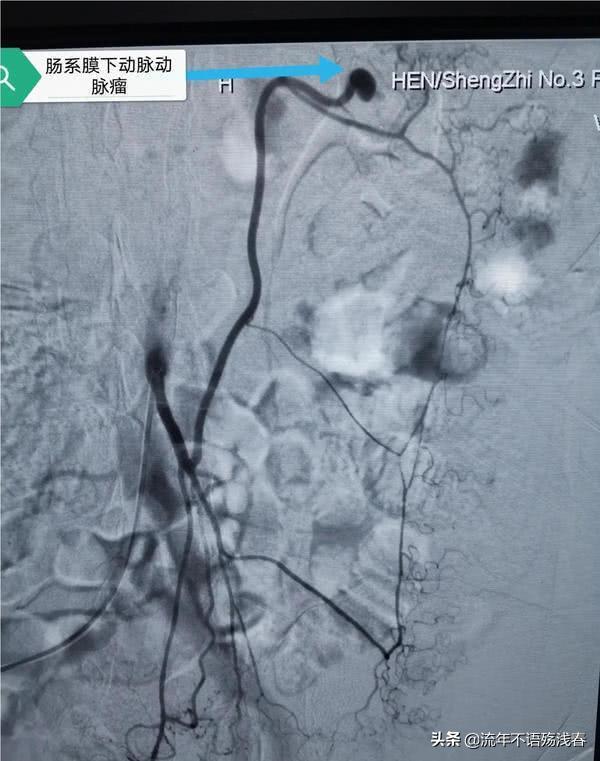

不久前,在河南,43岁的王先生在和同事斗嘴的时候,挨了女同事的一记小粉拳,打到了王先生的腹部,不久王先生居然腹痛难忍,被送到医院检查后,原来是正好打破了王先生的一个动脉瘤,现在王先生已经脱离危险,还要感谢女同事,因为女同事提前打破动脉瘤,避免了日后恶化的危险!